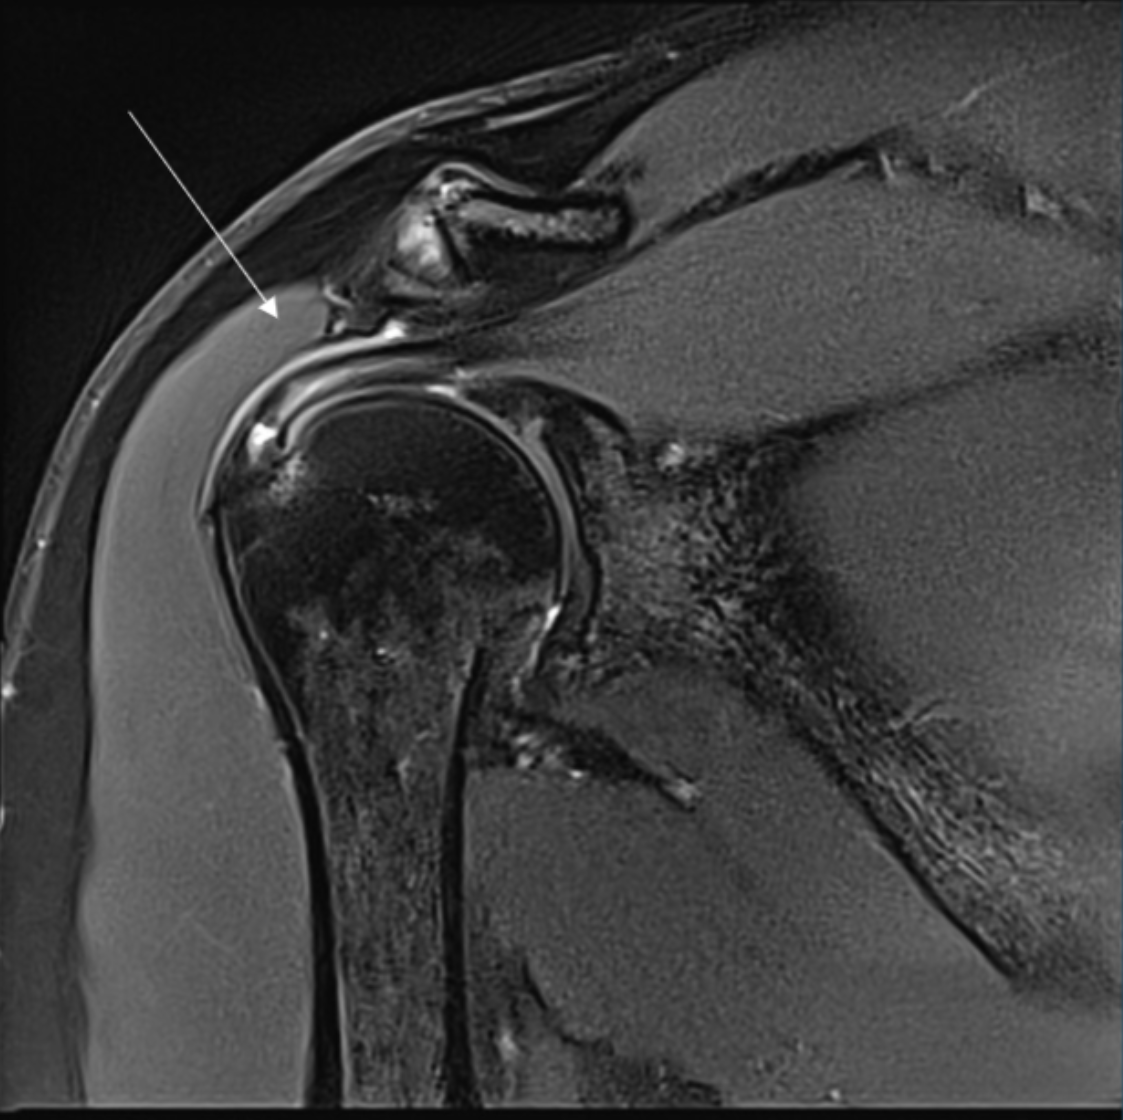

Describe the pathology indicated by the arrow (Cor T2 FS).

Supraspinatus tendon tear